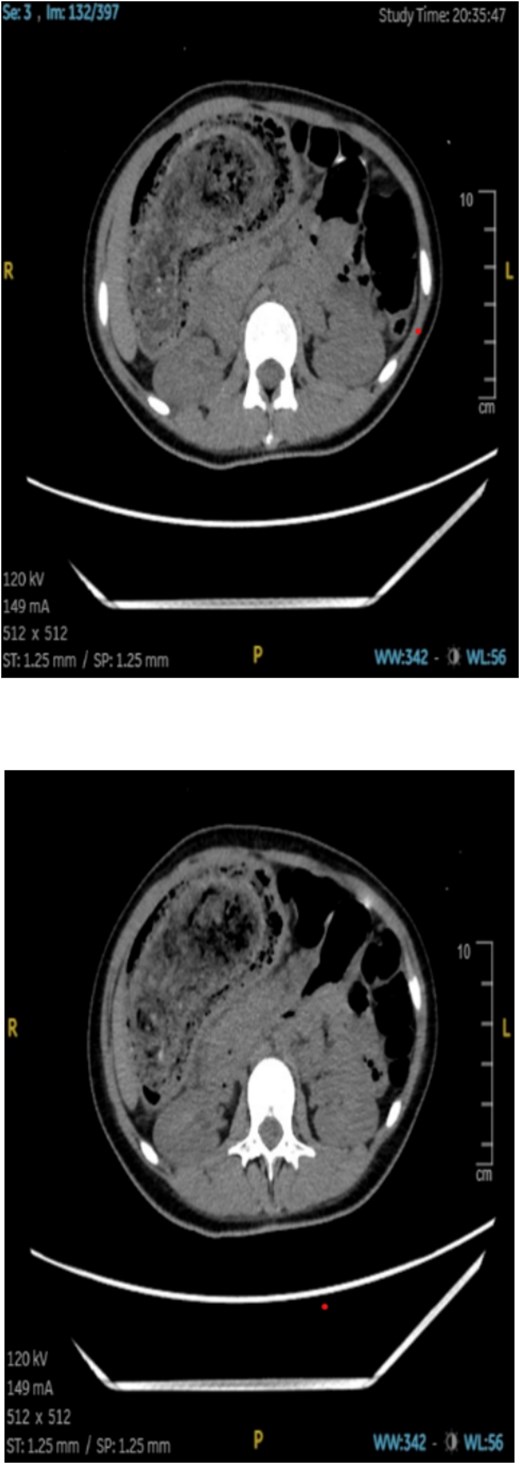

An abdominal CT scan showed a large, intragastric mass with a characteristic mottled appearance and gas entrapment (Figs 1 and 2), consistent with a trichobezoar. The mass extended into the duodenum, confirming the diagnosis of Rapunzel syndrome.

The patient was scheduled for exploratory laparotomy under general anesthesia. Intraoperatively, a large trichobezoar composed of hair and undigested food material was identified and removed via a gastrotomy. The mass measured ~22 × 7 × 8 cm and had a tail extending into the duodenum (Fig. 3). The stomach and intestinal wall were intact, with no evidence of ulceration or perforation. The postoperative course was uneventful, and the patient was started on intravenous fluids, antibiotics, and analgesics. Oral feeding was gradually resumed, and she was discharged in stable condition 5 days after surgery.

CT imaging played a crucial role in the diagnosis; the characteristic “mottled gas” appearance of the mass helped differentiate the trichobezoar from other gastric masses or tumors. Upper GI endoscopy can also be diagnostic and therapeutic in smaller cases, but large bezoars like the one described typically require surgical removal.